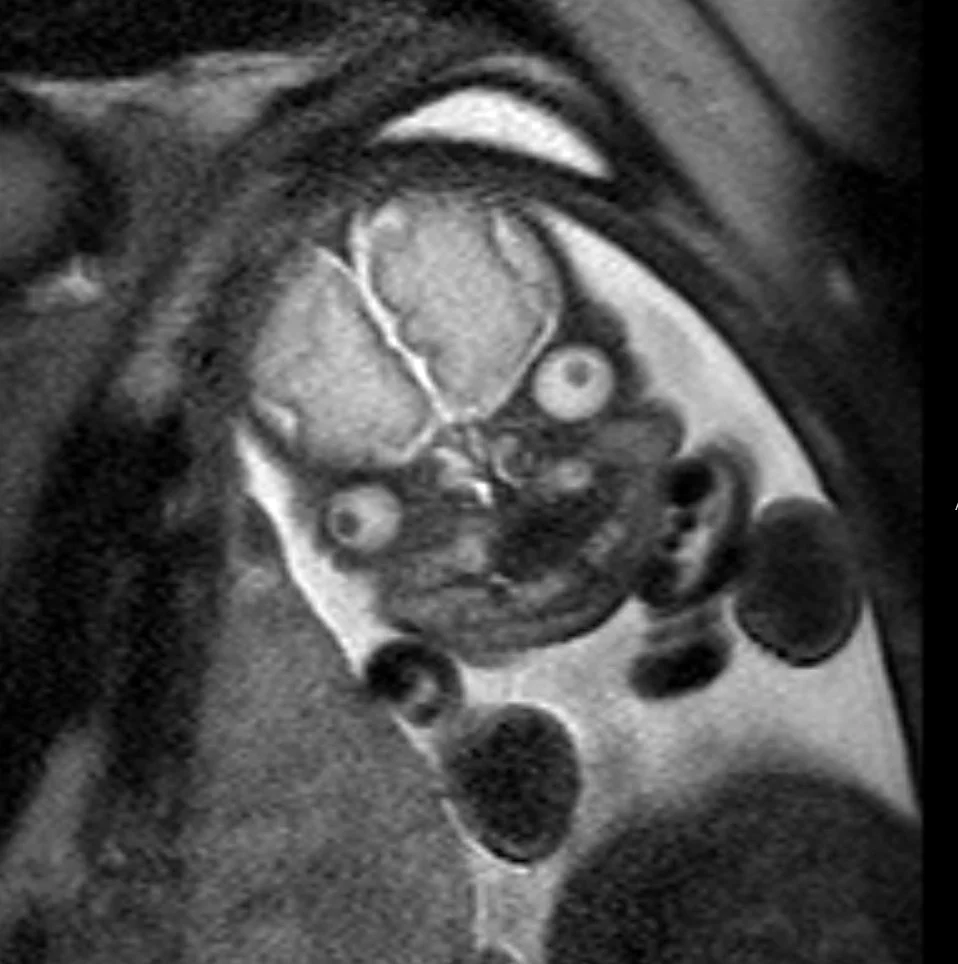

Master your FRCR 2B examination with authentic, expert-created content. Access 1,250+ short cases (2,000+ radiographs) across 50 packets, plus 600+ long cases (1,000+ cross-sectional images) in 100 packets. Every image is a full lossless DICOM at diagnostic workstation quality, following RCR display guidelines. No AI-generated content – all cases, questions, and answers are meticulously crafted by experienced radiologists.

Experience authentic FRCR 2B preparation with our professional DICOM viewer displaying full lossless images at diagnostic workstation quality. Access 1,250+ short cases and 600+ long cases – all created by expert radiologists with zero AI-generated content.

MyFRCR is the UK's premier FRCR 2B exam platform, offering 1,250+ authentic short cases with 2,000+ radiographs and 600+ long cases with 1,000+ cross-sectional images. Our commitment to non-AI, expert-created content with full lossless DICOM quality ensures candidates receive genuine exam preparation.

2,000+ radiographs and 1,000+ cross-sectional images in full lossless DICOM format.

Zero AI content – all cases created by expert consultant radiologists.